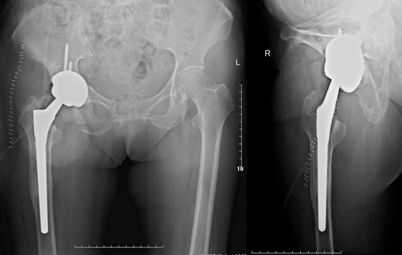

图6 70岁女性,THA术后1年松动,翻修术后仍有疼痛,生活不能自理

图8 第三次翻修术后3年,髋关节无痛,功能可,生活可以自理